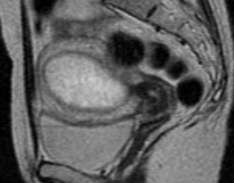

MR APPEARANCE OF PLACENTAL SITE GESTATIONAL TROPHOBLASTIC ...

JANUARY-MARCH 1996 MR APPEARANCE OF PLACENTAL SITE TROPHOBLASTIC NEOPLASM 61 Following the dilation and curettage, the B-HCG level was 45 IU. ... Return Doc